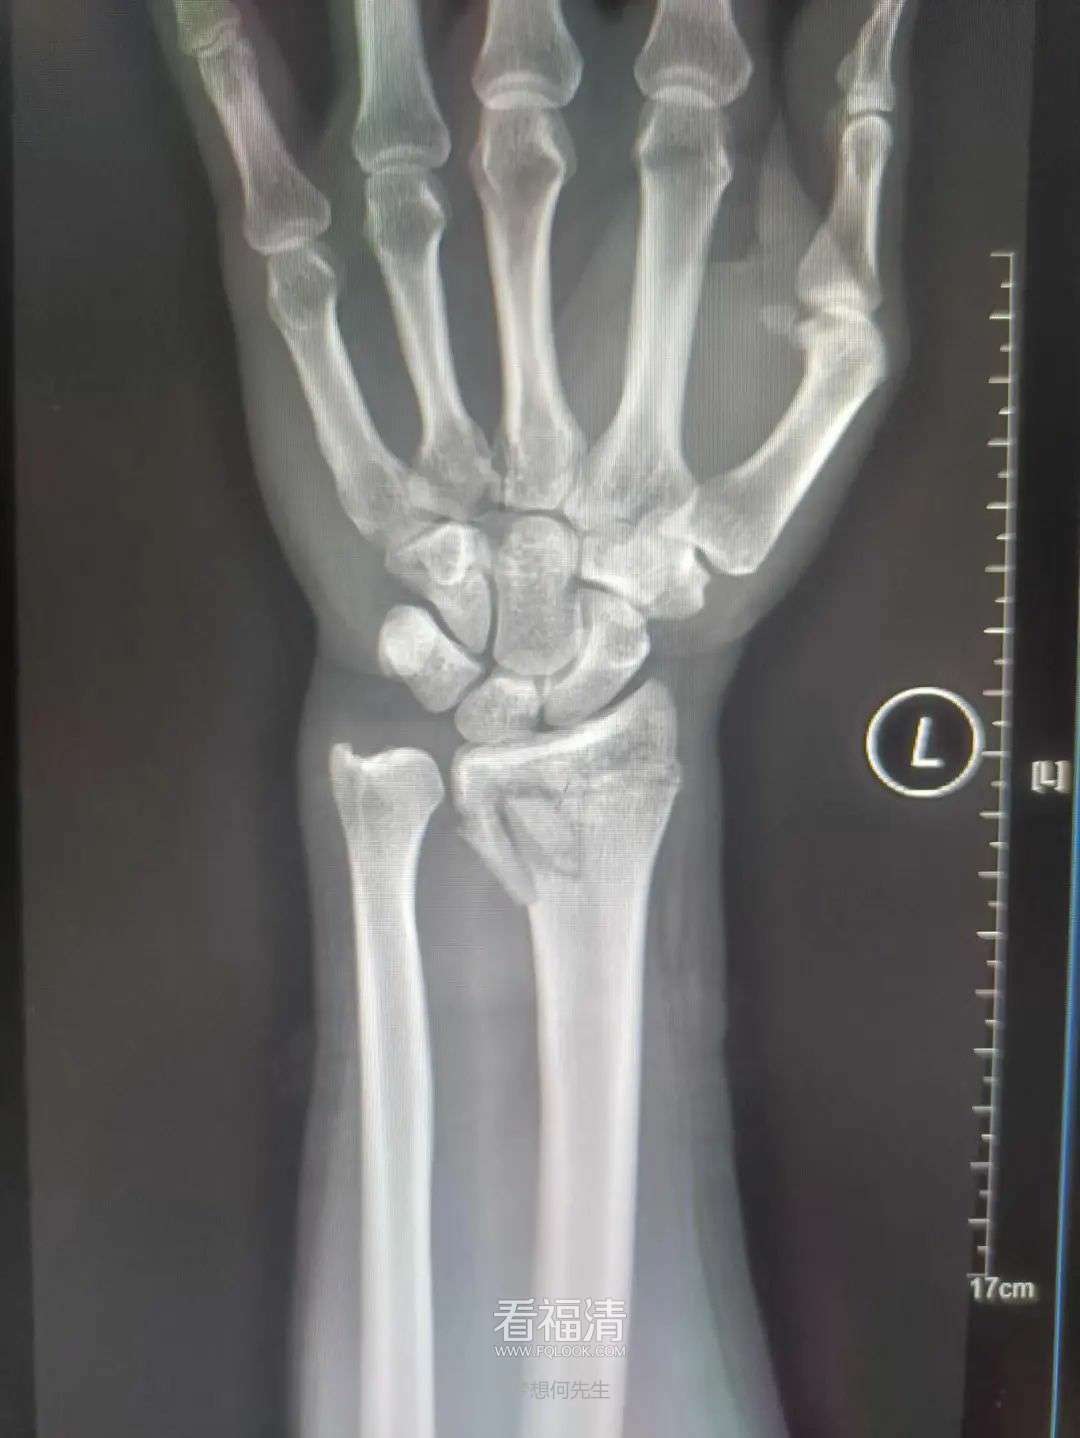

复位后

患者39岁,因外伤导致左手疼痛难忍,前来福清市第五医院中医骨科门诊寻求治疗。经过详细检查,患者被确诊为左侧桡骨远端粉碎性骨折伴下尺桡关节脱位。接诊的王征勇运用精湛的正骨手法进行复位,并在中医正骨理论的指导下,使用石膏进行固定。这种治疗方案有效地稳定了复位后的桡骨远端骨折,促进了骨折的愈合,避免了不必要的手术治疗,同时显著减轻了患者的疼痛感。